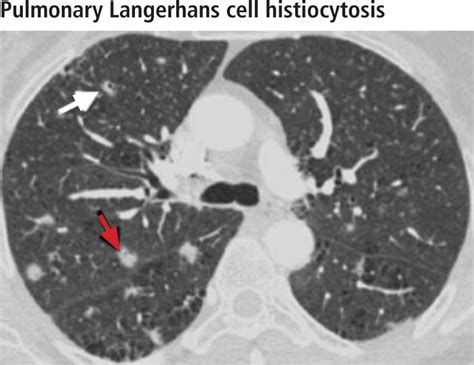

When your doctor discusses lung scarring on CT scan, they are looking at specific patterns that tell a story about the lung’s history. Radiologists often use specific terminology to describe the appearance of these changes. Here is a simplified table of common radiological findings and their general implications:

Radiological Term What It Usually Implies

Reticulation A net-like pattern indicating mild thickening of the lung structure.

Honeycombing Clusters of cystic air spaces; often suggests advanced or established scarring.

Ground-Glass Opacities Hazy areas; these may indicate active inflammation that could be reversible, rather than permanent scar tissue.

Traction Bronchiectasis The pulling open of airways due to the contraction of surrounding scar tissue.

💡 Note: A radiological term does not equal a diagnosis. Your physician must correlate these imaging patterns with your medical history, blood work, and physical examinations before confirming any specific lung condition.